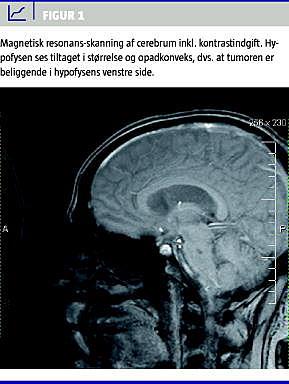

Pga. fund af hyperprolaktinæmi blev patienten akut henvist til videre udredning og behandling i endokrinologisk regi. Patientens hyperprolaktinæmi blev verificeret ved to kontrolmålinger, der viste prolaktinkoncentrationer på hhv. 10.400 og 14.800 MIE/l (60-250 MIE/l). Prolaktinforhøjelse af denne størrelse er diagnostisk for et makroprolaktinom. Hyperprolaktinæmi udløst af anden sygdom, tilstand eller medikamentel behandling kunne således afkræftes. Der var relativ hypogonadotrop hypogonadisme og normal inhibin-B/follikelstimulerende hormon-ratio. Øvrige hypofyseakser viste normal insuline-like growth factor -1 samt synactentest, og TSH-koncentration på 4,08 MIE/l (0,35-4,00) med thyroxinkoncentration på 95 nmol/l (70-140) og frit koncentration af thyroxin på 14,9 pmol/l (14,0-23,0). En MR-skanning af hypofysen viste et makroadenom, der målte 13 × 13 × 13 mm (Figur 1 ).

Ved gennemgang af patientens tidligere MR-skanninger af cerebrum fandt man, at adenomet var til stede et år tidligere og på daværende tidspunkt målte 7 × 7 × 7 mm. En neurooftalmologisk undersøgelse viste normale synsfelter.